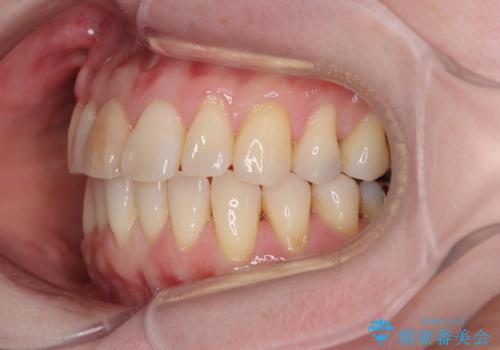

前歯のデコボコをインビザライン・モデレートで矯正治療

- 上下前歯のデコボコを気にして来院された患者様です。

安価なインビザラインパッケージを用いての治療を希望されており、デコボコの程度が中等度であったため、インビザライン・モデレートを用いて矯正治療を行うこととしました。